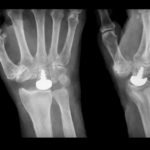

Posterior Malleolar Fracture for FRCS Orth

Courtesy: Rajesh Kakwani, FRCSOrth, Northumbria Health Care, UK